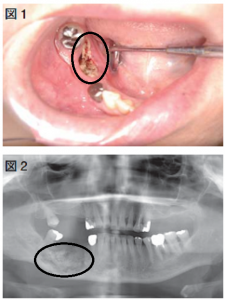

図1:歯肉から壊死した骨が露出している 図2:レントゲンで骨の溶解が確認できる

「顎骨壊死」とは名前の通り、顎の骨が壊死する病気で、主に骨粗しょう症やがんの骨転移に用いられる薬が原因で、抜歯が引き金で起こることが多いです。

この顎骨壊死を起こす薬はたくさんありますが、飲み薬では「空腹のときに飲んで30分飲み食いしないでください」と指示のある薬、あと定期的に注射する薬です。

ビスホソホネート製剤やデノスマブという薬ですが、大腿骨骨折や圧迫骨折を予防する効果の高い良い薬です。

私は、大学病院、病院歯科でこの顎骨壊死の治療に携わってきましたが、一度発症するとなかなか治りません。

ただ、顎骨壊死は腫れや痛みによる生活の質の低下を起こしますが、命を奪うことはほとんどありません。